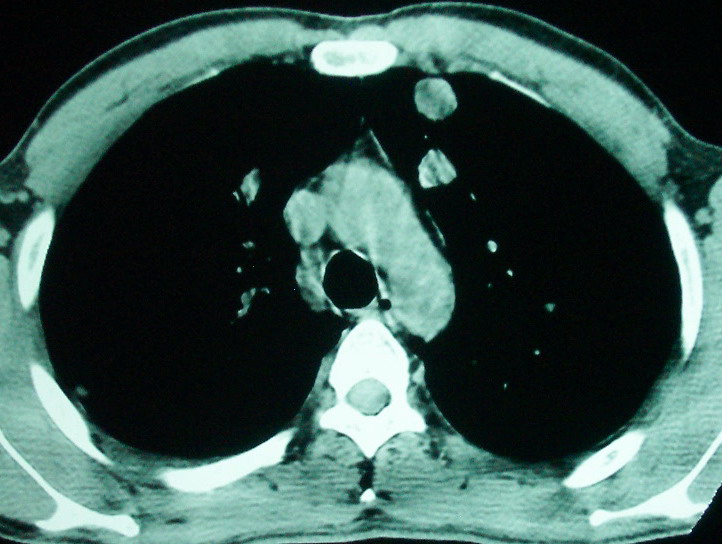

1、左下肺鳞癌伴两肺及纵隔淋巴结转移;

2、两上肺支扩伴慢性炎症。

鳞癌肺肺转移:厚壁空洞,洞壁厚薄不均,内似有壁结节,肺脓肿临床有无提示,血像如何?病灶周围很干净,没有明显渗出,很勉强?

如果你仔细的同层面对比,你会发现所有的病灶均有比较明显的吸收、缩小。病变的形态,特别是脓肿的形态、壁的厚薄、内壁均有很大的变化,均在往好的方面发展。与临床症状、血像均符合,治疗效果比较显著,就是肺脓肿并双肺的化脓性炎症灶。